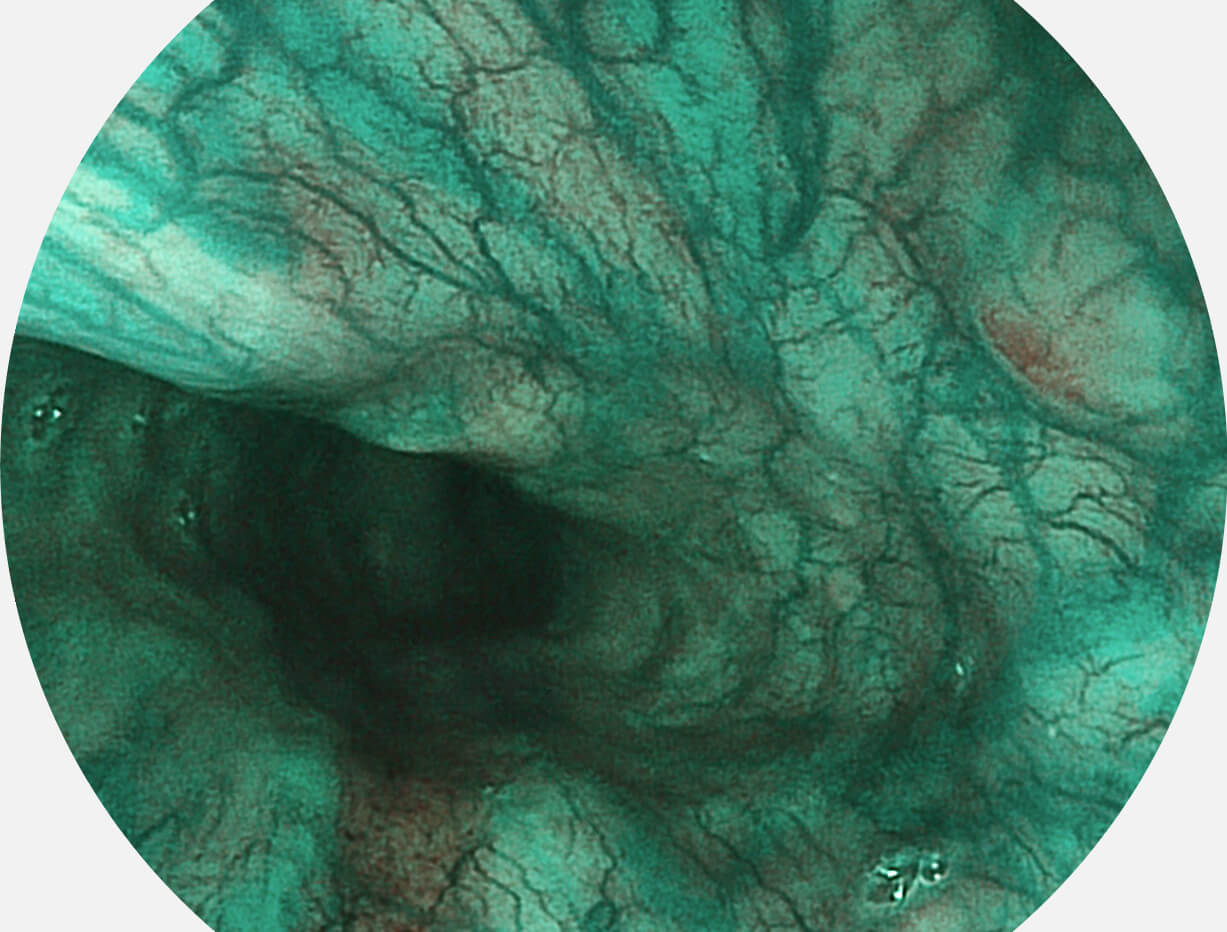

聚谱成像技术

Spectral Focused lmaging, SFI

图像具有高亮度、高黏膜血管颜色对比度的特点,且不改变粘液、食物残渣、粪便的基本颜色,可在中远景下进行观察,助力消化道早期疾病的诊断。

• 白光图像 SFI图像